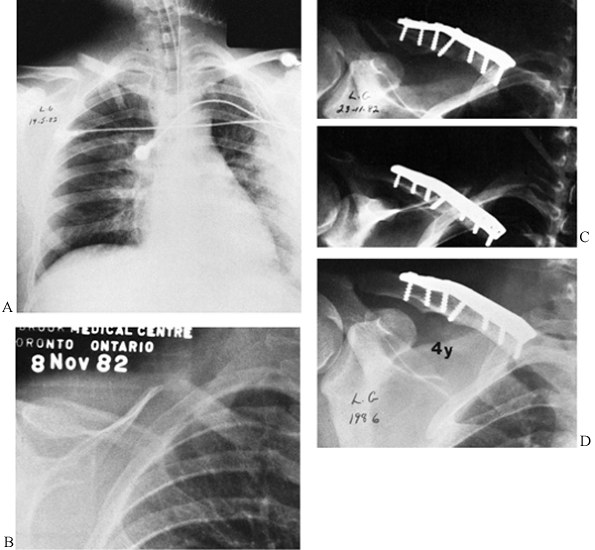

Figure 27.2. Nonunion of the clavicle. A: A midshaft oblique fracture of the right clavicle at the time of injury. B: Six months after nonoperative treatment, this fracture is still grossly displaced and mobile with no evidence of union. C:

Open reduction and internal fixation using a 3.5 mm dynamic compression

plate. Notice the oblique lag screw across the nonunion site. A bone

graft was also added. D: At 4 years,

consolidation has occurred. The patient is asymptomatic and has not

requested that the internal fixation be removed.